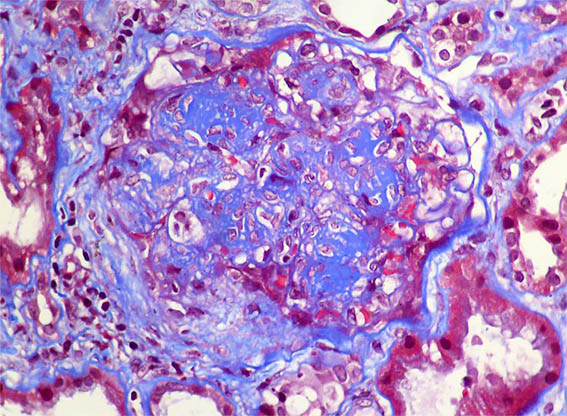

Figure 4. Masson's trichrome stain, X400.